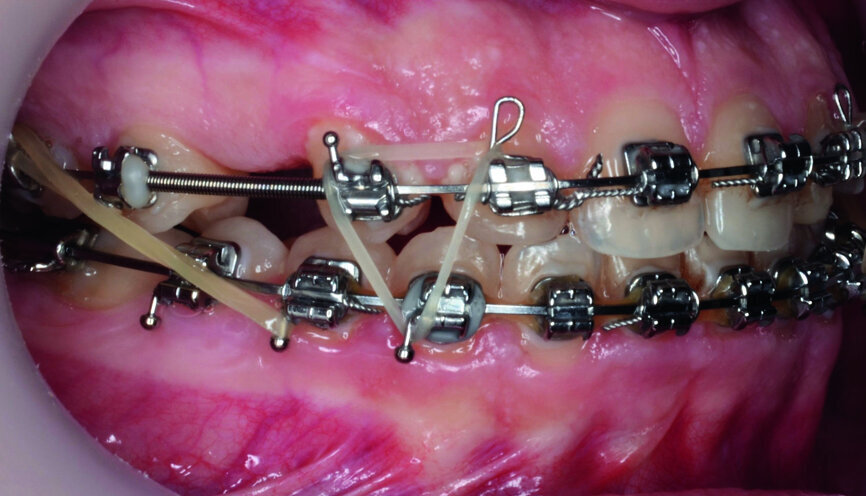

- Upper bracket placement (Fig. 22): level and align the gingival margins, and correct the torque on the upper canines who will substitute the lateral incisors.

- Implants space opening: substitute laterals with canines (Figs. 23–25) and substitute canines with first premolars (Figs. 26–28).